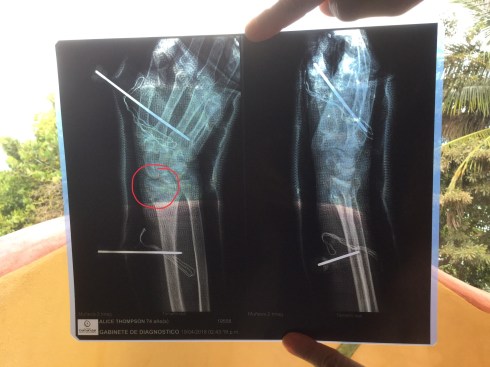

Wrist broken in multiple places.

My sweet mother in law was tripped by her kitty and went down hard on her right wrist. Surgery, pins and a cast oh my.